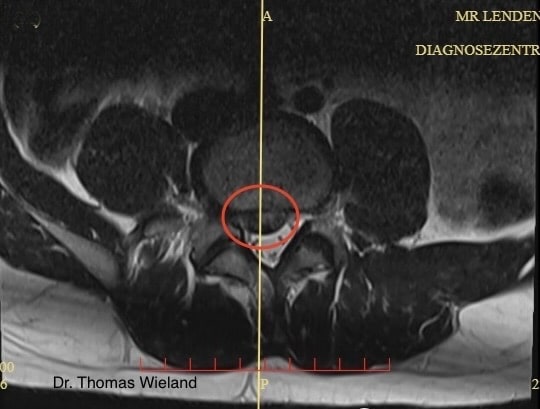

Schmerzen an der Wirbelsäule können unterschiedliche Ursachenhaben, die sich von Fehlbelastung bis hin zu Fehlhaltung ziehen. Eine genaue Anamnese und Untersuchung liefern Aufschluss darüber, woher die Rückenschmerzen kommen. Stammen die Schmerzen von einem Problem an der Wirbelsäule, muss dies systematisch und rasch behandelt werden. In vielen Fällen haben die Bandscheiben etwas mit den Schmerzen zu tun: ein Bandscheibenvorfall oder eine -vorwölbung sind häufige Ursachen für Rückenschmerzen.

Wichtig ist bei Rückenschmerzen eine genaue Untersuchung durch einen Spezialisten. Damit kann in neun von zehn Fällen schwere Erkrankungen ausgeschlossen und eine gezielte weitere Diagnostik (Röntgen, MRT, etc.) angeordnet werden.